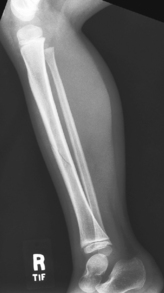

• Recumbent, affected side down

• Place unaffected limb behind patient to prevent over-rotation.

• Place support under distal portion of affected foot as needed to ensure a true lateral position of foot, ankle, and knee.

• Include ≈3 cm (1-1.5″) minimum beyond knee and ankle joints considering divergent rays